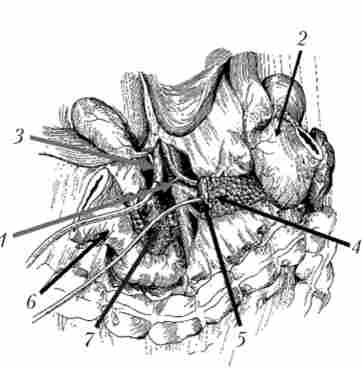

радикальні операції можливі лише у 6-30% хворих на рак ПЖ. Ці операції технічно важкі, що пояснюється складними тонографо- анатомічними взаємовідносинами ПЖ з прилеглими органами і великими судинами, особливо з ворітної веною.

Радикальною операцією при раку головки ПЖ вважається панкреатодуоденальная резекція (стандартна ПДР, операція Уиппла) - втручання, при якому видаляється головка ПЖ разом з дванадцятипалої кишкою, дистальним відділом загальної жовчної протоки, дистальної частиною шлунка (рис. 21.18). Етапи ПДР представлені на рис. 21.19-21.23.

Класична панкреатодуоденальная резекція - операція Уиппла

Мал. 21.18. Класична панкреатодуоденальная резекція - операція Уиппла:

1 - шлунок; 2 - дванадцятипала кишка; 3 - підшлункова залоза

Видалення панкреатодуоденальную комплексу. Органокомплекси фіксований на прошитою сшивающим апаратом У О (праворуч від верхньої брижової вени) дванадцятипалій кишці і крючковидного відростку

Мал. 21.19. Видалення панкреатодуоденальную комплексу. Органокомплекси фіксований на прошитою сшивающим апаратом У О (праворуч від верхньої брижової вени) дванадцятипалій кишці і крючковидного відростку:

Реконструктивний етап ПДР

Мал. 21.20. Реконструктивний етап ПДР.

У-образно відключена петля тонкої кишки, яка проведена позаду ободової кишки і розташована таким чином, щоб не було перекругов і натягу. Кишка П-образними швами підшита до культі ПЖ, в ній намічено отвір, що збігається з головним панкреатичним протокою при підведенні кишки до ПЖ: 1 - загальний жовчний протік; 2 - кукса підшлункової залози;

3 - брижа поперечної ободової кишки

Реконструктивний етап ПДР. формування холедохоеюноанастомоза

Мал. 21.21. Реконструктивний етап ПДР. Формування холедохоеюноанастомоза:

1 - загальний жовчний протік; 2 - тонка кишка; 3 - дренаж

Панкреато- і холедохоеюноанастомоз сформовані на дренажах

Мал. 21.23. Панкреато- і холедохоеюноанастомоз сформовані на дренажах:

1 - холедохоеюноанастомоз; 2 - панкреатоеюноанастомоза

Продовження етапу формування панкреатоеюноанастомоза

Мал. 21.22. Продовження етапу формування панкреатоеюноанастомоза. Нитками прошиті задня стінка головного панкреатичного протоку і кишка через всі шари. Дренажна трубка проведена через просвіт кишки і виведена назовні:

1 - тонка кишка, 2 - підшлункова залоза; 3 - дренаж